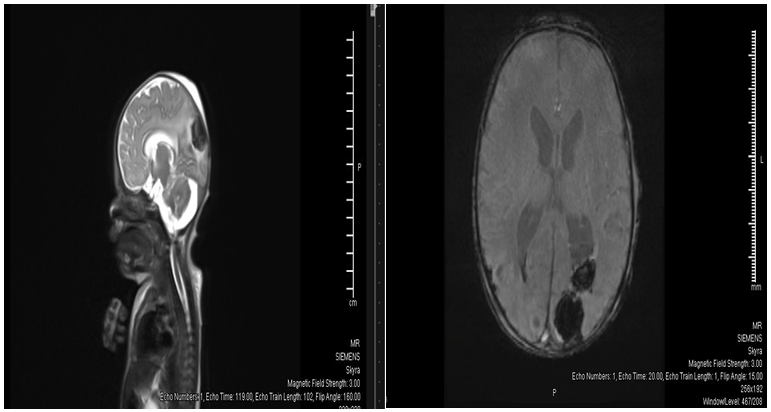

Brain ultrasound showed Bilateral grade I IVH with small hematomas at germinal matrix regions and small cerebral hematoma noted in the right occipital lobe measures about 11x14mm with prominent cisterna magna(figure 3). MRI scan at age of 5 days revealed Posterior fossa retro cerebellar cyst suggestive of Dandy-Walker spectrum malformation, Intracranial hemorrhage with right occipital and left occipitoparietal hematomas, bilateral cerebellar microhemorrhages and intraventricular hemorrhage and Mild to moderate supratentorial hydrocephalus(figure 4). The patient developed severe Thrombocytopenia started on the first day. Platelet count was 23,000 needed frequent PLTs transfusions, improved within 4 days to 123,000. The patient developed seizures at two weeks with lip smacking controlled well by Phenobarbitone. Neurosurgery and neurology team managed intracranial bleed conservatively. Last brain ultrasound: no detectable new fresh blood clots seen, Lateral ventricular dilatation. V/H ratio=32:84mm, Residual degenerated blood clots in the occipital horn of left lateral ventricle measures 12x10mm, re-demonstrations of Dandy-Walker spectrum malformation changes.

Figure 3 Ultrasound Brain showing Resolving bilateral grade II IVH with small degenerated blood clots in the lateral ventricles Posterior fossa retro cerebellar cyst suggestive of Dandy-Walker spectrum malformation. Bilateral occipital cerebral hematomas starting degeneration measure 17x10mm on the right side and measures 17x12mm on the left side.

Figure 4 MRI brain Posterior fossa retrocerebellar cyst suggestive of Dandy-Walker spectrum malformation. Mild to moderate supratentorial hydrocephalus.

Nonspecific central nervous system structural abnormalities documented by neuroimaging may be observed in over half of affected individuals, with an increased frequency of ventriculomegaly reported.11 In our case the FMU scan revealed ventriculomegaly and features of Dandy-Walker spectrum malformation. Intracranial haemorrhage with Rt.occipital and left occipitoparietal haematomas, bilateral cerebellar microhemorrhages and intraventricular haemorrhage were also found in our patient.